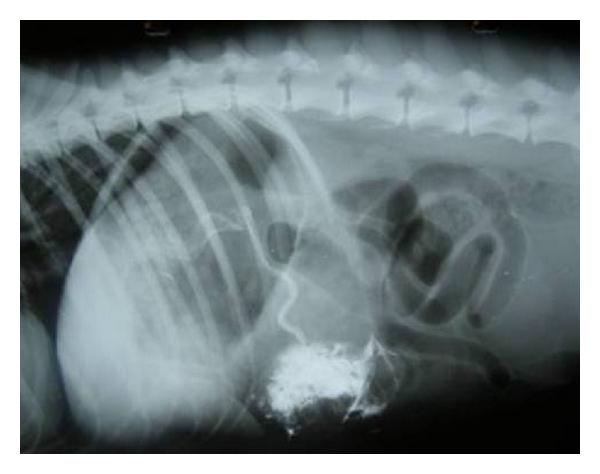

Hepatic disease is often treatable and has a predictable prognosis when a definitive diagnosis is made. The aim of clinicopathological evaluation of hepatobiliary affections is to identify and characterize hepatic damage and dysfunction, identify possible primary causes of secondary liver disease, differentiate causes of icterus, evaluate potential anaesthetic risks, assess prognosis and response to xenobiotics, and monitor response to therapy. This paper describes the different diagnostic methods and imaging techniques employed in diagnosis of hepatobiliary affections in dogs. Besides reviewing the significant clinical manifestations and imaging structural abnormalities in diagnostic approach to different hepatic affections, it also depicts radiographic, ultrasonographic, and wherever applicable, the laparoscopic characterization of different hepatic affections and target lesions encountered in clinical cases presented in the Teaching Veterinary Clinical Complex, COVAS, Palampur in the year 2007-2008.

肝病通常是可治疗的,一旦做出明确诊断,其预后是可预测的。肝胆疾病临床病理评估的目的是识别和描述肝损伤及功能障碍,确定继发性肝病可能的主要病因,鉴别黄疸的病因,评估潜在的麻醉风险,评估预后及对外源化学物质的反应,并监测治疗反应。本文描述了用于诊断犬肝胆疾病的不同诊断方法和成像技术。除了回顾不同肝病诊断方法中的重要临床表现和成像结构异常外,还描述了2007 - 2008年在帕兰普尔兽医临床综合教学中心(COVAS)出现的临床病例中不同肝病及目标病变的放射学、超声学特征,以及在适用情况下的腹腔镜特征。